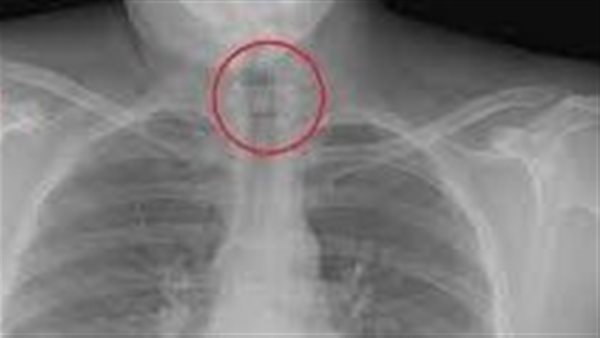

عند وصول فريق الإسعاف، قام الطاقم الطبي بالإجراءات اللازمة لاستخراج الدبوس من حلق الطالبة، وتم التعامل مع الحالة بحرفية لضمان عدم حدوث أي مضاعفات. وبعد استخراج الدبوس، تابعت الفرق الطبية حالة الطالبة بدقة قبل نقلها إلى المستشفى للاطمئنان على صحتها بالكامل.